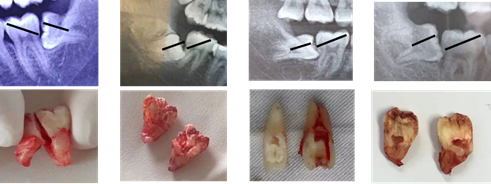

Figure 1 Proximal mesial impacted tooth extraction using two-line parallel split tooth method. A) Parallel lines design based on orthopantomography (OPT). B) Flap development and exposure of impacted tooth. C) tooth sectioning following the parallel lines using dental drill. D) Removal of distal part of the tooth. E) Removal of mesial part of the tooth. F) The impacted tooth.

Figure 3 AxialExtraction of proximal mesial impacted tooth following the above method.